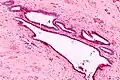

It is characterized by cysts with tubal-type epithelium (e.g. ciliated epithelium) surrounded by a fibrous stroma. It is not often associated with hemorrhage.

Endosalpingiosis is occasionally found in lymph nodes, and may be misinterpreted as an adenocarcinoma metastasis.[6]

Intermed. mag.